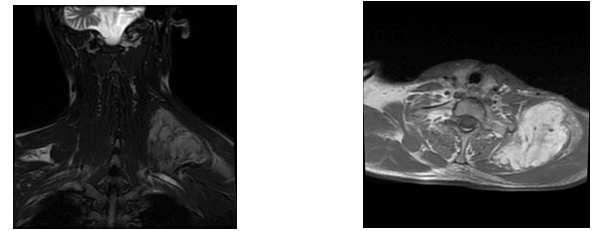

AbstractLeiomyoma is a benign soft tissue neoplasm originating from smooth muscles. While leiomyomas most frequently occur in the uterine myometrium (95%), they are also found in the skin (3%), gastrointestinal system (1.5%), and in less than 1% of cases in the head and neck region . The tumor generally appears in the 4th and 5th decades of life, more commonly in females, and typically presents as a slow-growing, asymptomatic lesion.The main treatment for leiomyoma is surgical resection, and recurrence is quite rare. In this case report, we present a rare case of a giant solid leiomyoma located in the supraclavicular region, which we evaluated clinically, histopathologically, and radiologically IntroductionLeiomyoma is a benign neoplasm arising from smooth muscle cells and is most commonly found in the uterus, skin, and gastrointestinal tract. However, due to the limited presence of smooth muscle tissue in the head and neck region, leiomyomas in this area are extremely rare, accounting for less than 1% of all cases. These tumors generally present as slow-growing, painless masses and are more frequently observed in middle-aged women. Histopathologically, leiomyomas consist of bundles of well-differentiated spindle cells with eosinophilic cytoplasm and show strong immunoreactivity for smooth muscle markers such as smooth muscle actin (SMA), desmin, and caldesmon. Based on histological features, leiomyomas are classified as solid leiomyoma, vascular leiomyoma (angioleiomyoma), and epithelioid leiomyoma. Although their pathogenesis remains unclear, theories suggest that they may originate from the vascular smooth muscle of small blood vessels or pluripotent mesenchymal cells. Surgical excision remains the mainstay of treatment, and recurrence is uncommon. In this report, we present a rare case of a giant solid leiomyoma located in the supraclavicular region, evaluated clinically, radiologically, and histopathologically. Case ReportA 33-year-old male presented to the Otorhinolaryngology Department of Antalya Training and Research Hospital with a complaint of swelling in the left supraclavicular region for six months, which had gradually increased in size. On physical examination, a firm, fixed, smooth-surfaced, tender mass approximately 7x5 cm in size was palpated in the left supraclavicular area. Neck ultrasound revealed a heterogeneous hypoechoic mass lesion originating from muscle tissue on the left lateral neck measuring 78x68x36 mm. MRI of the neck showed a mass lesion located posteriorly in the left supraclavicular region with a maximum size of 91x58 mm, hyperintense on T2-weighted images, and intensely enhanced after intravenous contrast administration (Figure 1). Fine-needle aspiration (FNA) biposy was and diagnosis of a benign spindle cell benign tumor was made.